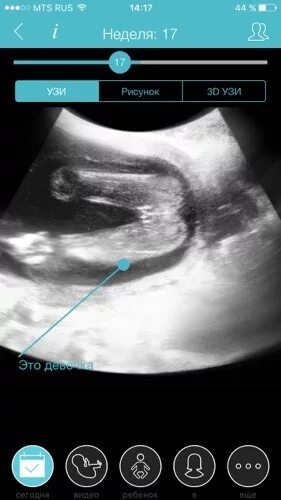

Может врач ошибиться с полом ребенка